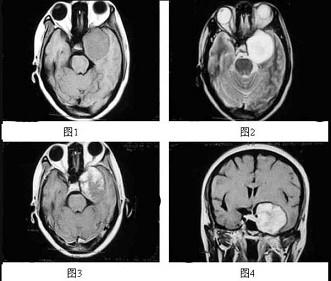

问题 女,47岁,左侧面部麻木2个月余,伴阵发性头痛、耳鸣,MRI检查如图所示,最可能的诊断为()

选项 A.三叉神经纤维瘤 B.海绵状血管瘤 C.脑膜瘤 D.颅咽管瘤 E.胶质瘤

答案 B